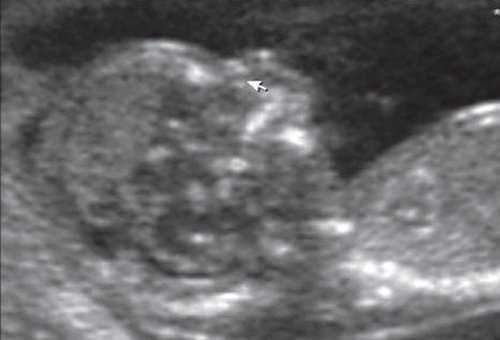

Для качественной оценки особенностей строения нижней челюсти в I триместре беременности специалистами МГО МОНИИАГ совместно с профессором W. Sepulveda (Чили) был изучен и впервые описан новый ультразвуковой признак нижнечелюстной промежуток (mandibular "gap"), визуализируемый при первом скрининговом ("генетическом") ультразвуковом исследовании [18, 19].

Методика базируется на изучении коронарного скана лица плода, так называемого ретроназального треугольника, при котором визуализируется верхняя и нижняя челюсть. Техника получения этого скана чрезвычайно проста и может быть рекомендована для скринингового исследования в 11-14 нед беременности. Эта методика позволяет оценить нижнюю челюсть плода без применения трудоемких оценок, и не сопряжена с математически сложными расчетами коэффициентов, также она существенно не увеличивает время осмотра. Коронарный скан можно оценивать как в режиме 2D, так и в режиме объемной эховизуализации 3D. Методика оценки коронарного скана лица плода в I триместре беременности показана на рисунке 6.

Рис. 6. Методика оценки коронарного скана лица плода в I триместре беременности.

Обе ветви нижней челюсти при сроке 11-14 нед беременности выглядят гиперэхогенными, а в месте слияния имеют характерный гипоэхогенный промежуток, ультразвуковой "разрыв". Этот признак визуализируется при нормальном развитии нижней челюсти (mandibular "gap").

При патологии нижней челюсти (микрогнатии) в срок 11-14 нед беременности при изучении коронарного скана лица нижнечелюстной "промежуток" отсутствует, нижняя челюсть представлена единой, слившейся костной массой. Отсутствие нижнечелюстного "промежутка" (mandibular "gap") при эхографии в этот срок является маркером гипоплазии нижней челюсти (микрогнатии). Варианты отсутствия нижнечелюстного промежутка при микрогнатии при различных синдромах в срок 11-14 нед беременности представлены на рисунке 9.

Рис. 9. Отсутствие нижнечелюстного промежутка при микрогнатии, при различных синдромах нехромосомного генеза в 11-14 нед беременности.

Оценка описанного признака при проведении пренатальной эхографии I триместра беременности не только проста в методологии и не требует больших затрат по времени исследования, но и высоко информативна, диагностически точна и специфична.